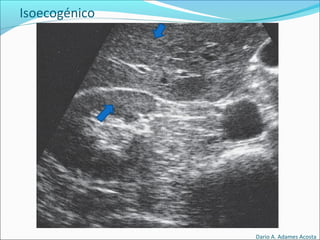

Patrones Ecográficos

Escala de grises

Depende de la densidad de los elementos y capacidad

para producir Ecos.

Isoecogénico

El elemento que nos interesa es de color similar al resto

de elementos circundantes(igual densidad).

Isoecogénico

Isoecogénicos